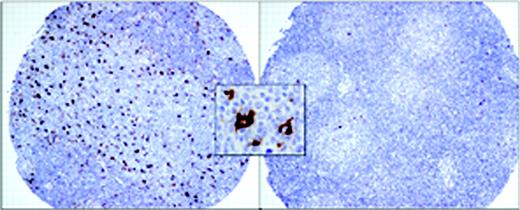

Representative tissue microarray cores of patients with follicular lymphoma. The image on the left shows the uncommon finding of large numbers of macrophages both within and surrounding neoplastic follicles (n = 12). The image on the right shows the more common finding of very few macrophages (n = 87). The insert shows the typical strong cytoplasmic staining of reactive macrophages with anti-CD68 antibody. Images were acquired using a Nikon Eclipse E600 clinical microscope and Dxm1200 digital camera and software (Nikon, Tokyo, Japan). Original magnification × 100 (objective, 10 ×/0.3 NA) for the larger panels and × 1000 (objective, 100 ×/1.3 NA) for the insert.

CD68+ macrophages were first evaluated for their consistency between duplicate cores and then qualitatively. The initial analysis of CD68 staining revealed that macrophage content could be divided into 2 groups, cases with either none or few cells positive versus many positive cells. To make the determination of macrophage numbers more objective, we counted cells using high-power magnification (× 1000 oil lens). This high magnification was used to avoid counting neutrophils and intercellular debris occasionally stained with this antibody. Five representative fields per case were counted. We chose to count in areas where the staining was the strongest and most uniform. In virtually all of the cases scoring was made easier by the fact that cases were either clearly positive or negative (Figure 1). Neither FDCs nor neoplastic B cells stained with anti-CD68 in any case.

The FDC pattern (CD21) was disrupted with expansion of the meshwork and fusion of the follicles in 27% of the cases. The reactive T cells showed a predominantly perifollicular distribution in most cases (70%), as well as a CD4 phenotype (76%). In 71% of the cases there was a unique follicular pattern, with CD4 cells inside the follicles surrounded by CD8 positive cells outside the follicles, whereas in other cases the distribution was diffuse for both subsets. CD57+ cells represented more than 10% of the T cells in most cases (64%) and they had a clear follicular pattern in 68%, with most of the positive cells localized inside the follicles. In 82% of these cases the CD57 follicular pattern correlated with the CD4/CD8 follicular pattern and both CD57 and CD4 cells had an equal distribution within the follicles. Cases with more than 10% cytotoxic TIA-1 granule+ cells were found in 45% of the cases. The numbers of CD68+ macrophages (LAMs) were initially determined using low-power magnification. None of the cases showed staining of neoplastic B cells with anti-CD68 antibody. It was clear that most cases had few or no macrophages, while a small number had many (Figure 1). The distribution of these CD68+ cells was uneven throughout cores with both intrafollicular and perifollicular macrophages observed. We then used high-power magnification (× 1000 oil lens) to count the CD68+ macrophages, which ranged between 1 and 25 cells per high-power field (hpf). Because many of the cases had no or few macrophages, we established a cut-off of 15 cells/hpf for analysis purposes. Importantly, most of the negative cases had less than 10 cells (82%), and the positive cases had more than 20 cells (58%) per hpf, respectively. Table 3 shows the distribution of clinical and pathologic variables for the FL cases with high LAM (n = 12) versus those with low LAM content (n = 87). Only histologic grade was unevenly distributed between these 2 groups and thus was included in a multivariate model along with the IPI. All biomarker determinations were measured without knowledge of the clinical outcome. Except for the LAM score, none of the other markers showed a significant impact on outcome. Cases with less and more than 15 CD68+ macrophages/hpf had median OSs of 16.3 and 5.0 years, respectively (P < .001; Figure 2). Figure 3 shows the progression-free survival curve. Cases with less and more than 15 CD68+ macrophages/hpf had a median PFS of 7.05 and 1.69 years, respectively (P = .001). A multivariate proportional hazards model that included the LAM content, the IPI score, and histologic grade showed that LAM is an independent predictor of OS (HR = 2.4, 95%CI = 1.3-4.5, P = .004). The inferior PFS and OS of the patients with a high LAM score cannot be explained by a lower response rate to treatment (Table 3), nor an increased risk of histologic transformation (0 of 12 developed transformed disease) nor lack of appropriate treatment for relapse (all patients with relapse were treated with systemic chemotherapy, 3 with high-dose chemotherapy and hematopoietic stem cell transplantation). All but 1 of the 10 deaths among the patients with high LAM scores resulted from progressive lymphoma.